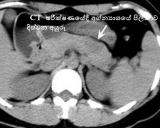

මෙහි පැතිරී ඇති ප‍්‍රමාණය ගැන අවබෝධයක් ලබා ගැනීම සදහා සීටී පරීක්ෂණ සිදුකරනු ලබයි.